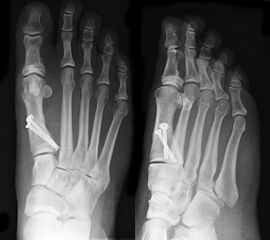

• Die Operationsplanung erfolgt anhand der Röntgenaufnahmen des Vorfußes unter Belastung in 2 Ebenen. Für die Verfahrenswahl sind wichtig der Intermetatarsalwinkel und die Breite des Os metatarsale, der Hallux valgus Winkel, der distalen Gelenkflächenwinkels (Distal Metatarsal Articular Angulation - DMAA), des Metatarsaleindex und Sesambeinposition (Abb. 1).

• Röntgenkontrollen (Vorfuß d.p. und seitlich) postoperativ ohne Belastung. Weitere Kontrollen erfolgen 6 Wochen, sowie 3, 6 und 12 Monate jeweils unter Belastung.